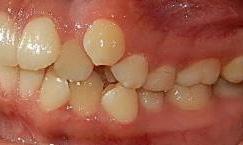

Estudios de inicio intraorales en la fotografía de frente, tenemos la línea media dental superior se encuentra desviada a 1 mm a la izquierda y la línea media dental inferior se encuentra desviada 2 mm a la derecha (Figura 2). En la oclusal superior la forma de arco cuadrada (Figura 3). En la lateral derecha una relación molar clase II y relación canina clase II (Figura 4), izquierda una relación

Dentista y Paciente 42 Caso clínico

molar clase II y relación canina clase II.